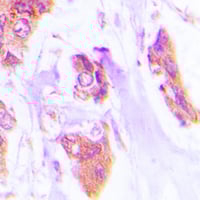

IHC (Immunohiostchemistry)

(Immunohistochemical analysis of Cardiotrophin-1 staining in human lung cancer formalin fixed paraffin embedded tissue section. The section was pre-treated using heat mediated antigen retrieval with sodium citrate buffer (pH 6.0). The section was then incubated with the antibody at room temperature and detected using an HRP conjugated compact polymer system. DAB was used as the chromogen. The section was then counterstained with haematoxylin and mounted with DPX.)